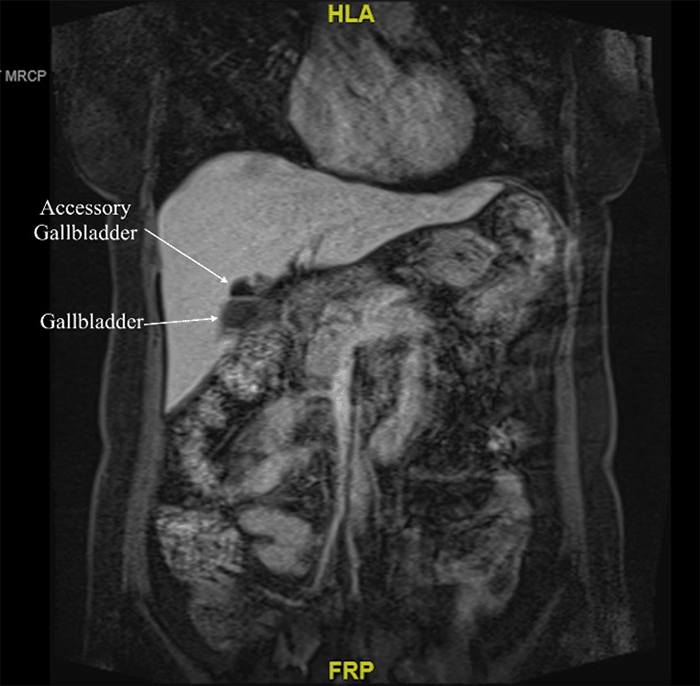

Figure 1. Abdominal Ultrasound Demonstrated Choledocholithiasis Within Presumed Right Intrahepatic Biliary Duct With Associated Duct Dilatation. Published with Permission

Her white blood cell count and liver function tests were within normal limits. Further workup showed gastritis on upper endoscopy. Her initial abdominal ultrasound from an outside facility did not detect any gallbladder anomalies but described choledocholithiasis within the right intrahepatic biliary duct with associated duct dilatation (Figure 1). These findings were subsequently confirmed with endoscopic retrograde cholangiopancreatography (ERCP); however, the stones were not retrieved out of concern for perforation and presumed need for surgical management. Following ERCP, the patient underwent magnetic resonance cholangiopancreatography (MRCP), which demonstrated an oblong, saccular gallbladder with a stone-containing accessory gallbladder or single dilated intrahepatic duct along the inferior inferomedial aspect of the right hepatic lobe, which was seen to communicate with the right hepatic duct (Figure 2).